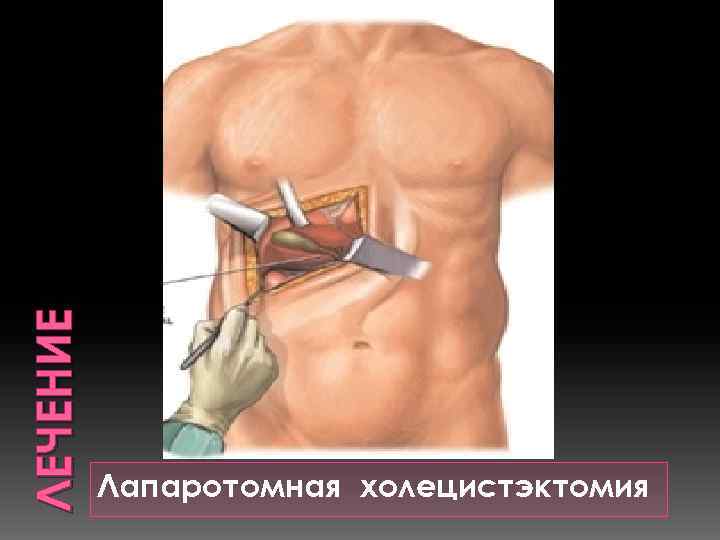

ЛЕЧЕНИЕ Лапаротомная холецистэктомия

ЛЕЧЕНИЕ Лапаротомная холецистэктомия